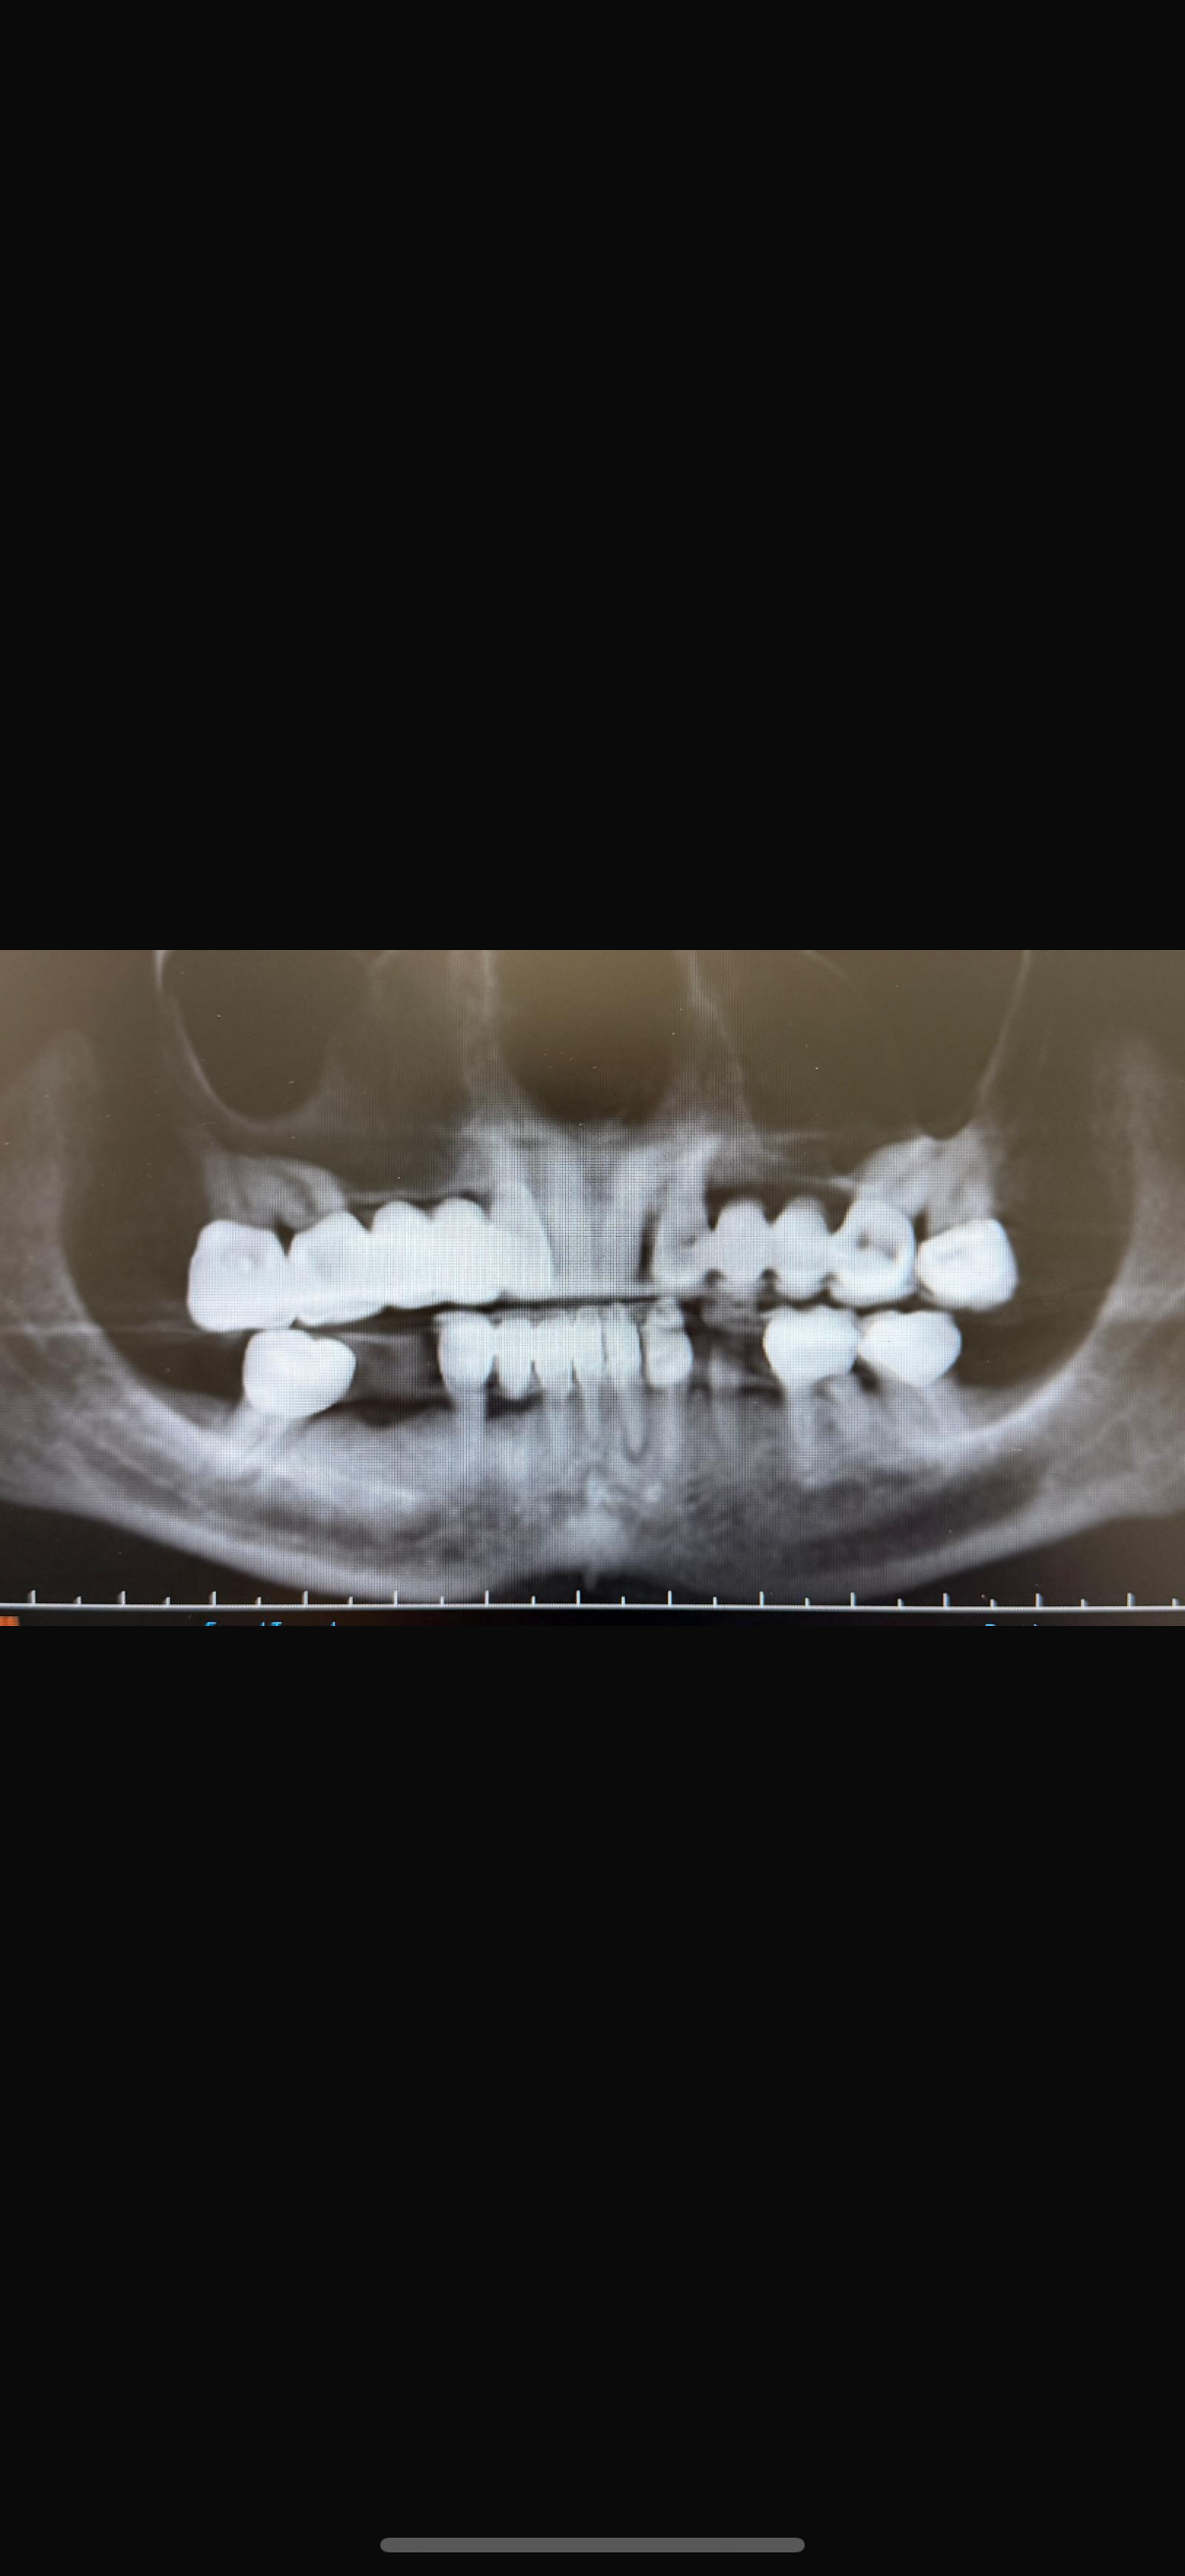

Black and white dental X-ray showing teeth, some of which are missing or damaged.

Case Selection

Dr. Damon will highlight the “Red Flags” of full arch, one of them being when the sinus extends anteriorly and touches the canine roots. We will discuss proper case selection, but also get you ready to take your next step in Full Arch—with remote anchorage.